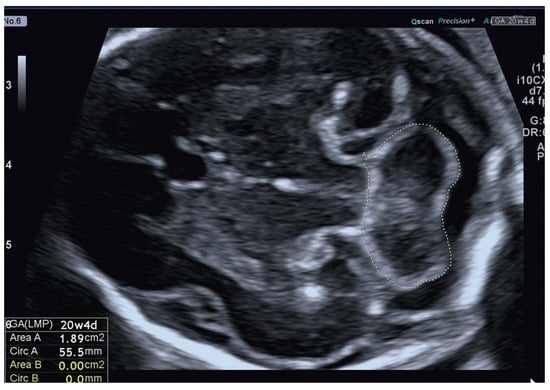

The 2D-US examinations were performed using standard Aloka (Aloka Co., Ltd., Tokyo, Japan) and Voluson E10 (GE Healthcare Ultrasound, Milwaukee, WI, USA) machines equipped with a curved linear array transabdominal transducer (2–5 MHz) and a transvaginal 4–8 MHz probe. The fetal cerebellum was assessed in the transverse plane of the fetal brain, including the cavum septum pellucidum, cerebellum, and cisterna magna, during fetal and maternal rest using a transabdominal acquisition angle of 45–60°, depending on GA. By focusing on this specific plane, the study ensured a standardized approach and consistent measurement technique across all participants. Freeze-frame capabilities allowed for the capture of static images at specific moments, enabling detailed analysis and precise measurements of the cerebellar area. Additionally, an electronic on-screen manual trace was employed to outline the boundaries of the cerebellar structures (Figure 1).

Figure 1. Assessment of the fetal cerebellar area by 2D-US transabdominal approach.